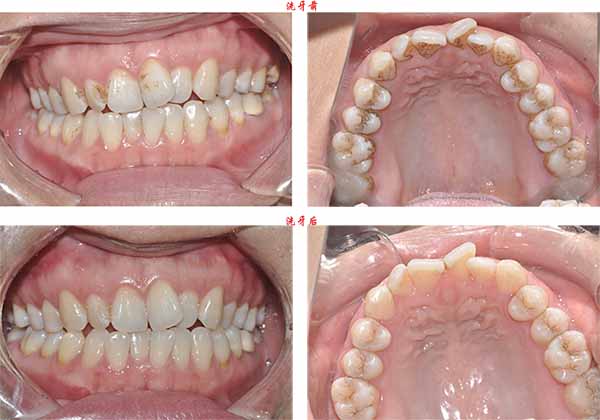

姓名:彭先生

主诉:牙齿色渍比较多,感觉不美观

治疗方案:超声波洗牙